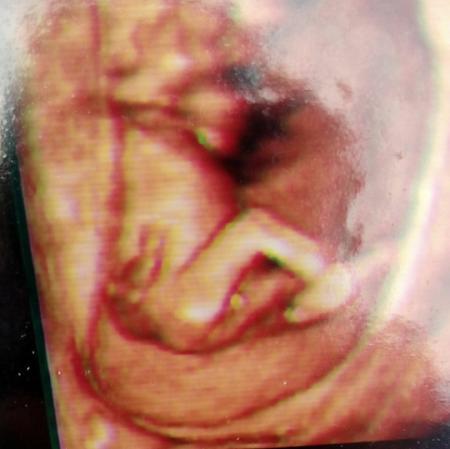

Habe selbst jedesmal in der 13ssw das Geschlecht erfahren Hatte allerdings 3 und 4D Aufnahmen. Hier von meinem Sohnemann

Bild zu